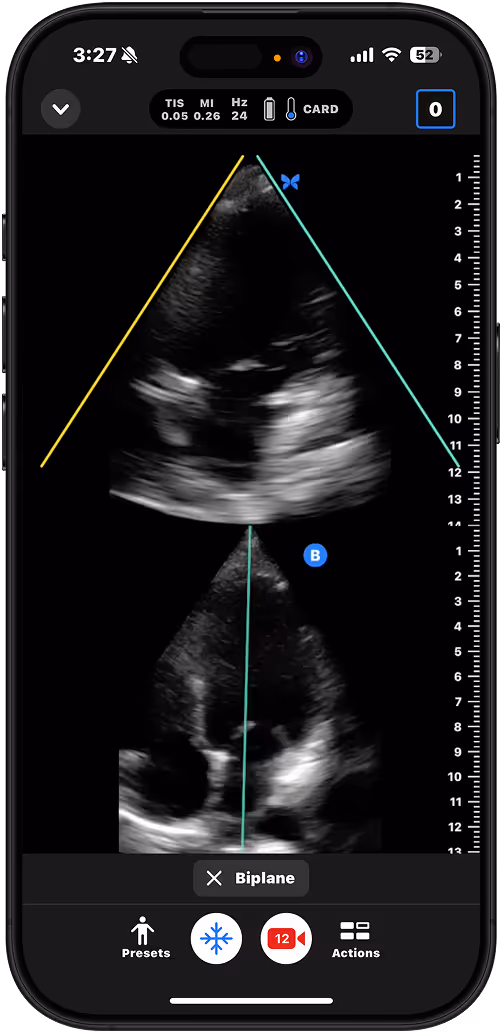

Assess for pericardial effusion or gross function in patients with chest pain or unexplained hypotension.

Long Aorta